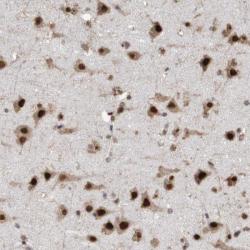

- Immunohistochemical staining of human cerebral cortex shows strong nuclear and cytoplasmic positivity in neuronal cells.

- Staining pattern consistent with experimental and/or bioinformatic data.